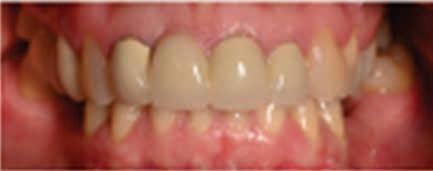

The patient continued to return to his pediatric dentist for routine dental check-ups and preventive visits. Figure 6 shows the clinical and radiographic appearance at 5 years after the traumatic intrusion. Root maturogenesis and apical closure of the maxillary left permanent central incisor is notable. The patient received orthodontic treatment when he was 14 years old, which was 7 years after sustaining dental trauma. Orthodontic treatment spanned one-and-a-half years, during the course of which the pediatric dentist monitored the

maxillary left permanent central incisor for any root and/or pulpal pathosis. Figure 7 shows the radiographic presentation of the tooth during and after orthodontic treatment.

Figure 6. Clinical and radiographic appearance at 5 years after intrusion injury.

Figure 7. Radiographic presentation of the tooth during and after orthodontic treatment (7-8